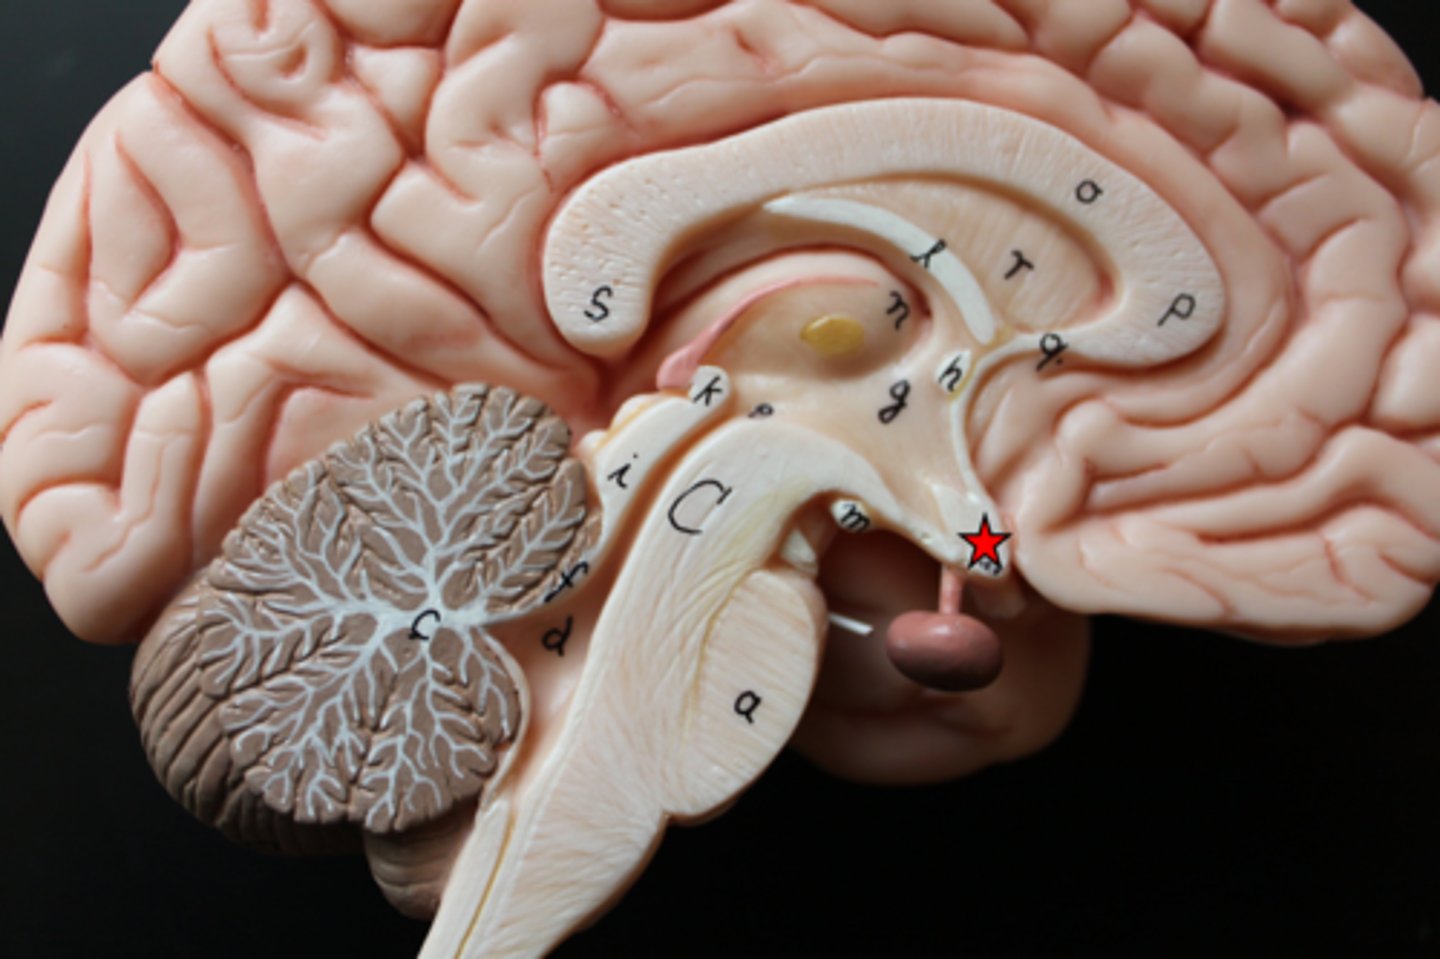

central sulcus

lateral sulcus

transverse fissure

precentral gyrus

postcentral gyrus

cingulate gyrus

longitudinal fissure

corpus callosum

septum pellucidum

optic chiasm

hippocampus

Interthalamic adhesion

Thalamus

Medial geniculate nucleus

lateral geniculate nucleus

Hypothalamus

Mammillary body

Pituitary gland

Pineal gland

Cerebellum

choroid plexus

lateral ventricles

cerebral aqueduct

third ventricle

fourth ventricle

pons

midbrain

medulla oblongata

olive

superior colliculi

inferior colliculi

cerebral peduncles

arbor vitae

Primary visual cortex

Primary auditory cortex

Primary fissure

Amygdala